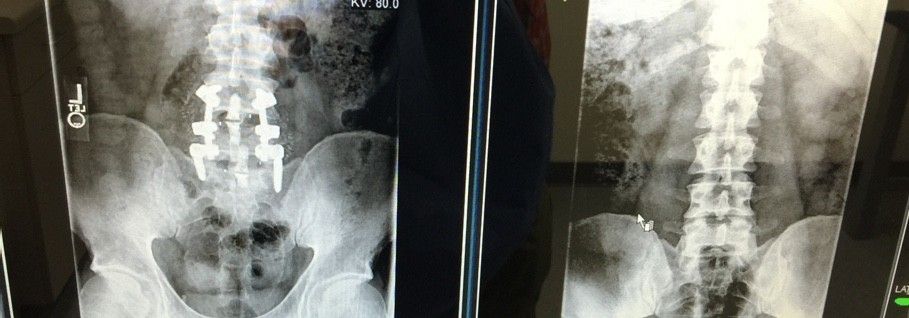

Here's my new titanium hardware. Should I compare it to the material that it replaced?

Power to the Metal! Damn, those screws look huge, though.Here's my new titanium hardware. Should I compare it to the material that it replaced?

Yeah they're pretty gnarly. I finally get to walk around without that damn uncomfortable brace now. Whew, that sh** has been rough!Power to the Metal! Damn, those screws look huge, though.